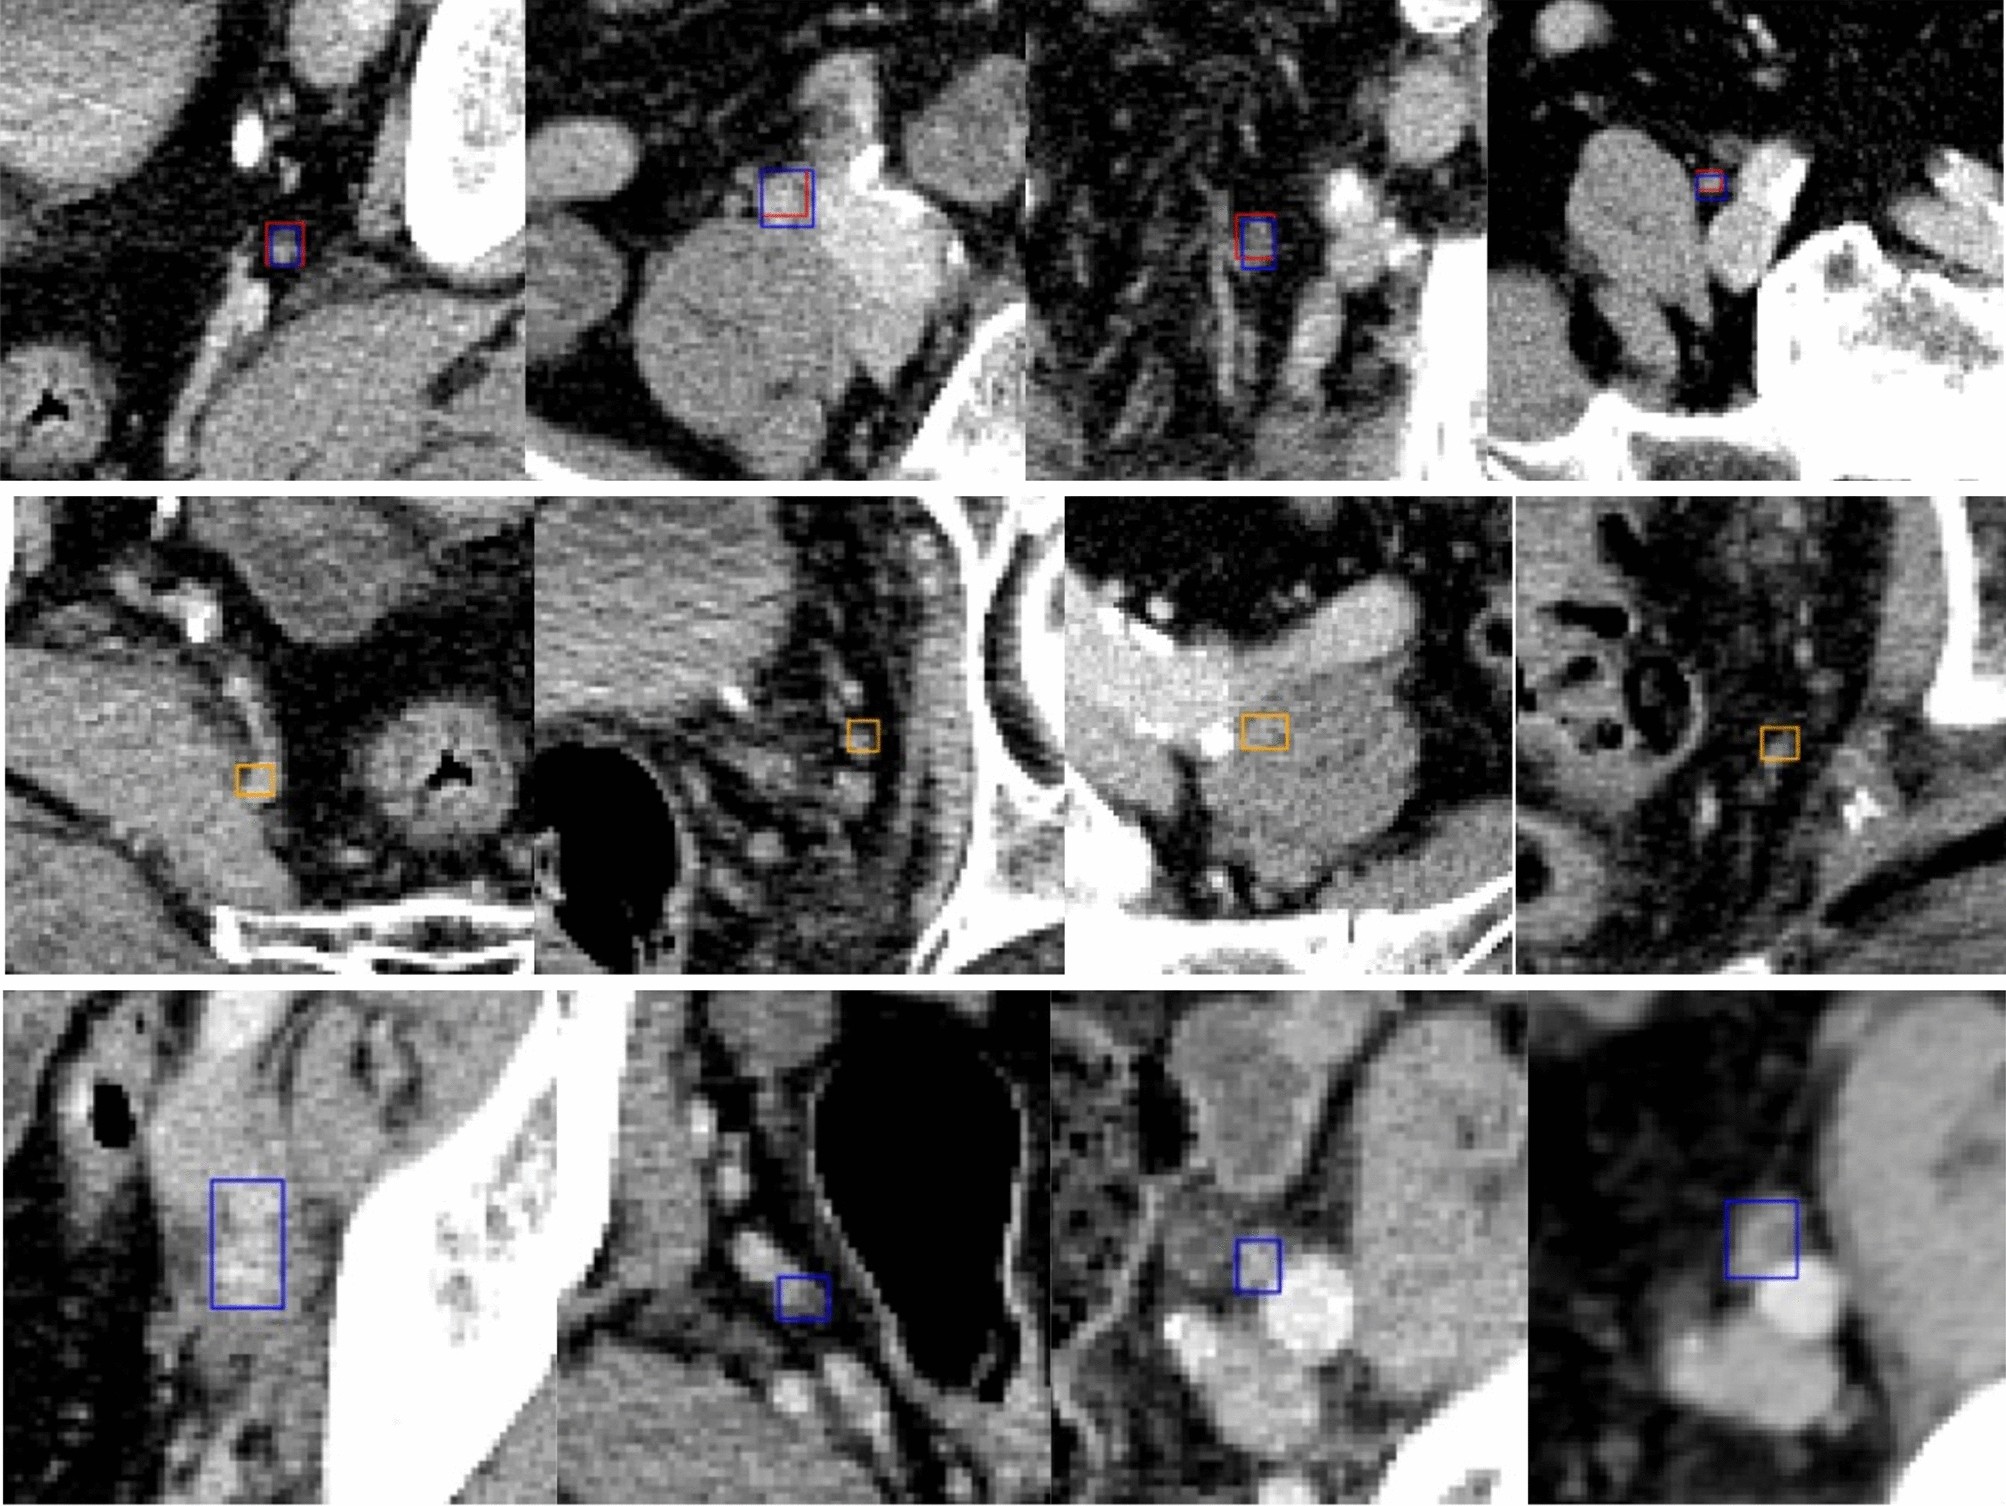

Figure 5

Examples of 2.5D Object Detection Pipeline Prediction on the test set. Images are zoomed in to better visualize the detection boxes. Boxes in red are TPs, in orange are FPs, in blue are GTs. The first row is the visualization of TPs, the second and last are for FPs and FNs, respectively.